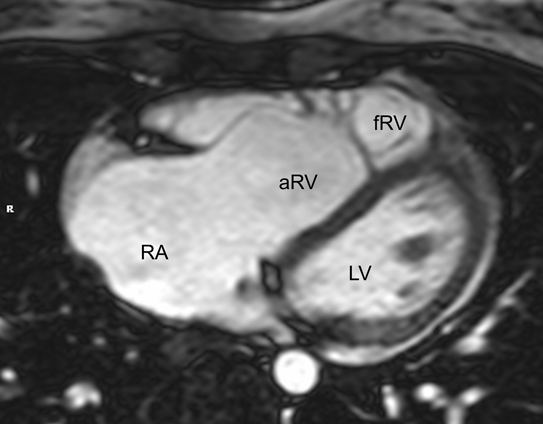

なお,右室容積計測には,右室全体を含む体軸横断像のシネMRIを代替的に用いることも可能である.これはエコーにおける四腔像に相当し,特にEbstein病の患者さんで,三尖弁前尖,中隔尖の形状,右房や心房化右室の大きさの評価に有用である.

シネMRIの撮影の項でも記載したが,右室容積計測には,右室全体を含む体軸横断像のシネMRIを代替的に用いることも可能である.これはエコーにおける四腔像に相当し,特にEbstein病の患者さんで,三尖弁前尖,中隔尖の形状,右房や心房化右室の大きさの評価に有用である(Fig. 9).

Pediatric Cardiology and Cardiac Surgery 40(4): 260-271 (2024)

Fig. 9 4-chamber long axis cine image of Ebstein’s disease

aRV, atrialization of the right ventricle; fRV, functional right ventricle; LV, left ventricle; RA, right atrium.